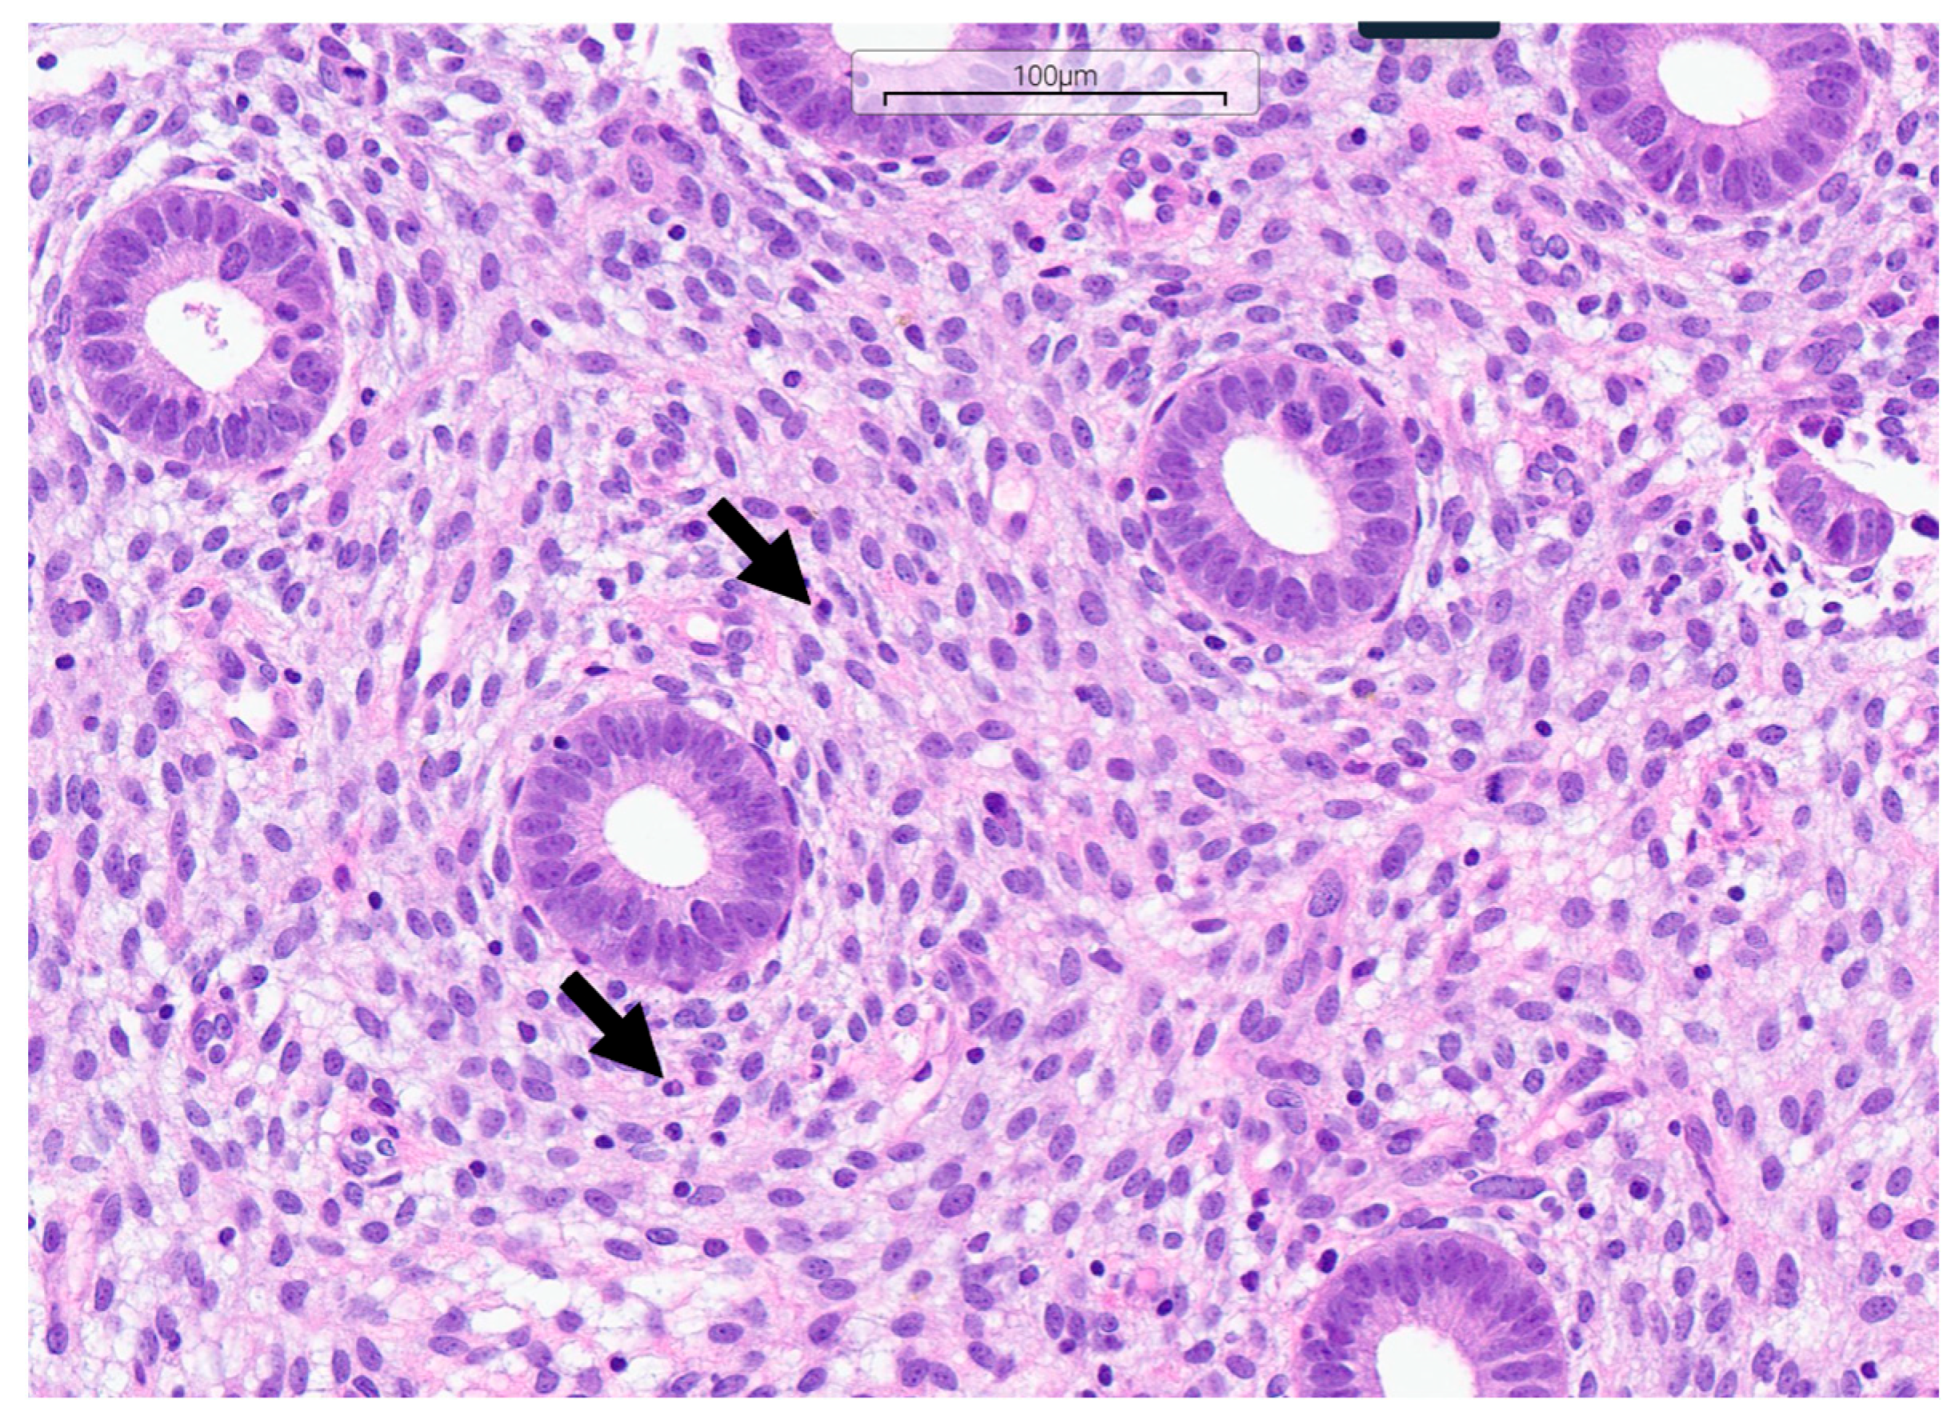

2.5. Histopathological Diagnostics